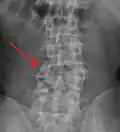

Diagnosis is by medical imaging.

A burst fracture of L4 as seen one plane X ray -